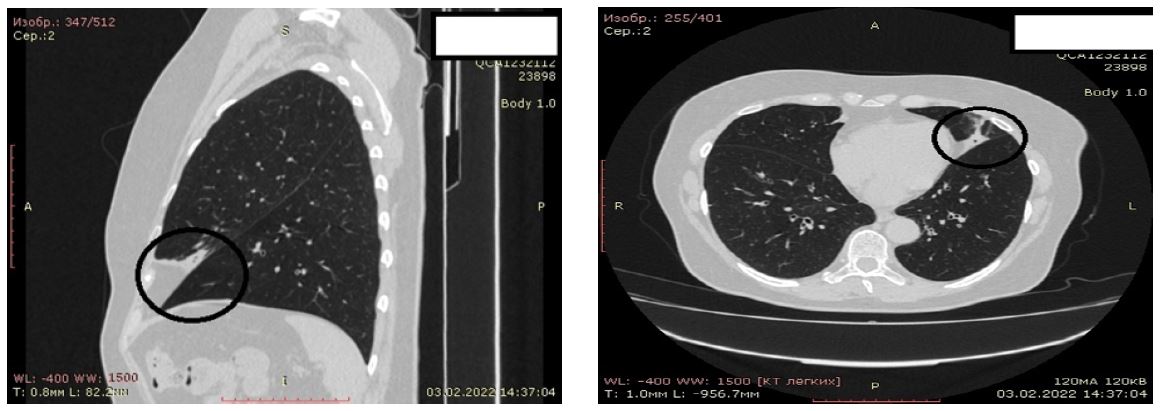

Обследования: МСКТ ОГК от 22 сентября 2022 г. рассасывание ателектаза в S4–5 слева и средней доле справа, бронхоэктазы в S4–5 слева. В S2 справа явления бронхиолита. Кальцинат в S1–2 справа, плевральные спайки (рис. 3).

Рис. 3. Пациентка Б. Компьютерная томография ОГК от 22 сентября 2022 г.: рассасывание ателектаза в S4 – 5 слева и в средней доле справа, бронхоэктазы в S4 – 5 слева